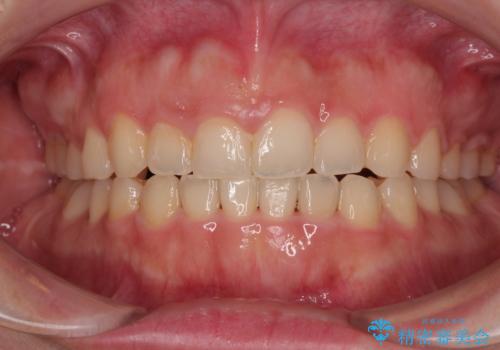

捻れて前に出ている前歯 ワイヤー装置での非抜歯矯正